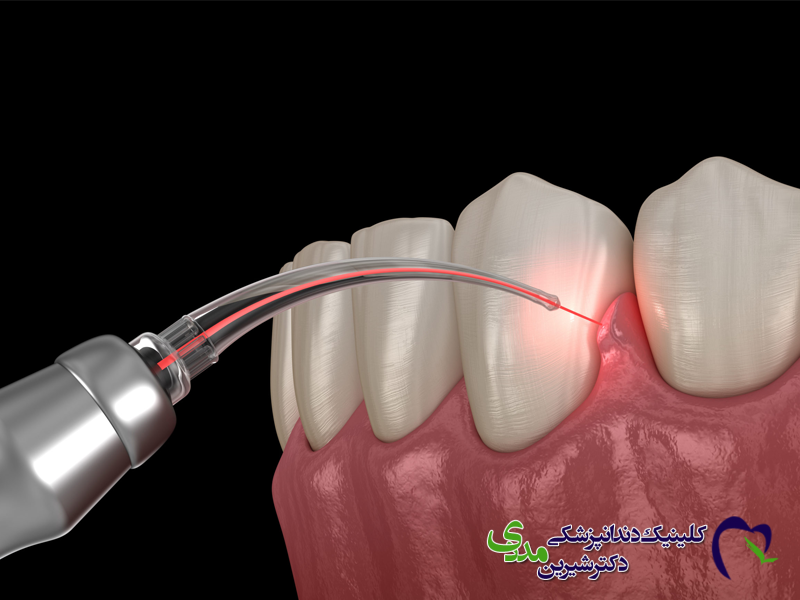

تفاوت در نوع جراحی

ایمپلنت: برای هر دندان، یک جراحی جداگانه (یا همزمان) نیاز است. حجم استخوان کافی برای هر ایمپلنت ضروری است.

اوردنچر: با تعداد جراحی های کمتری همراه است. همچنین در مواردی که استخوان فک تحلیل رفته است، امکان استفاده از ایمپلنت های زاویه دار یا خاص وجود دارد که نیاز به پیوند استخوان را کاهش می دهد.